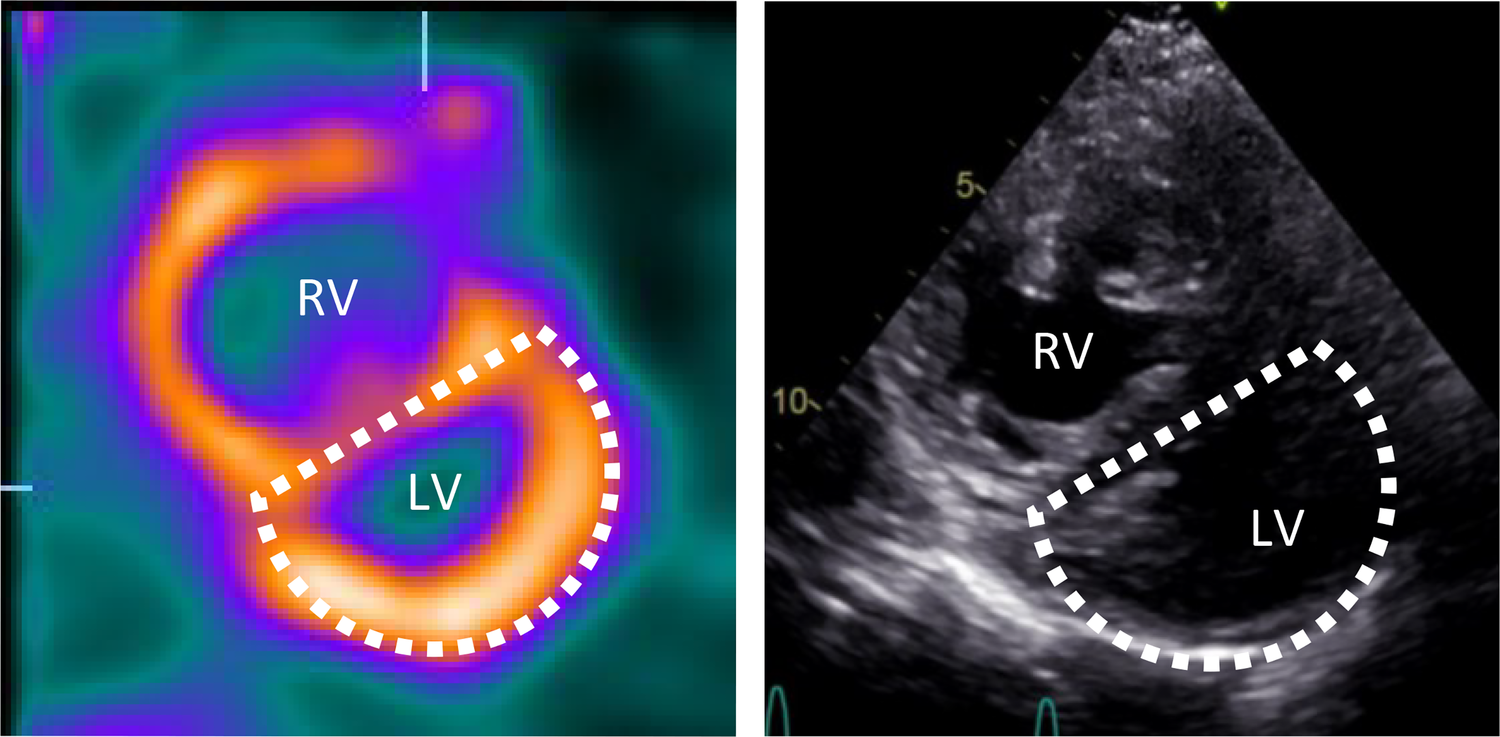

Figure 4

Movahed's sign on myocardial perfusion SPECT and D-shaped left ventricle on echocardiography. Short axis myocardial perfusion SPECT images at rest (left) and short axis view on transthoracic echocardiography (right) show the D-shaped left ventricle. SPECT, single photon emission computer tomography; RV, right ventricle; LV, left ventricle.

The D-shaped LV observed on myocardial perfusion SPECT was consistent with the analogous sign observed on echocardiographic short-axis views during systole (Figure 4). The perfusion defects were interpreted in relation to the RV pressure overload, with a low likelihood of coronary artery stenosis. Consequently, no additional diagnostic coronary angiography was performed. Furthermore, despite the progression of dyspnea, it was unlikely to be attributed to the small ischemic area without a clearly identifiable responsible vessel. Nevertheless, the option of a coronary CT or calcium scoring was discussed with the patient as a potential further diagnostic measure to fully rule out a CAD.

The displacement and loss of curvature of the septum can be best assessed in short-axis parasternal views in echocardiography and analogous to the short-axis views in myocardial SPECT (7) (Figure 4). When using the latter as a diagnostic modality, this sign must be carefully distinguished to avoid misinterpreting possible septal perfusion defects or global LV perfusion decrease caused by the hypervascularization or overload of the RV (13). In our case, the small septal ischemia after stress could potentially be attributed to increased intermural pressures rather than a mere coronary insufficiency. On the other hand, this finding may shed light on RV alterations due to ischemic left heart failure, particularly in the absence of structural right heart abnormalities or pulmonary disease (8). Indeed, Williams et al. previously showed that enhanced RV tracer uptake on stress SPECT perfusion imaging in patients with CAD could indicate an exercise-induced imbalance between RV and LV perfusion, potentially associated with severe CAD (13). In such a scenario, a coronary CT could be the optimal choice to exclude CAD, while a coronary angiography would be excessive due to the weaker association between the atypical ischemic pattern observed on myocardial perfusion SPECT and epicardial CAD, as well as the limited therapeutic implications resulting from the small risk area. Considering the patient's comorbidities and normal systolic function and wall motion, except for the septum, it is most likely that other factors were contributing to the dyspnea progression. Nevertheless, without a coronary CT, the presence of CAD cannot be definitively excluded.